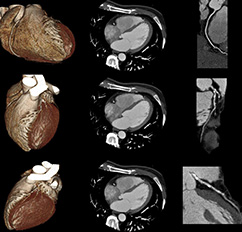

Die koronare Herzerkrankung (KHK) ist eine der häufigsten Erkrankungen in der westlichen Welt. Bei dieser Erkrankung führen Cholesterin- und Kalkablagerungen an der Gefäßwand (Arteriosklerose) zur Verengung der Herzkranzgefäße (Koronararterien). Diese Engstellen (Stenosen) vermindern die Blutversorgung des Herzmuskels. Kommt es mit dem Fortschreiten der KHK zum Gefäßverschluss, entsteht ein Herzinfarkt. Die Computertomographie des Herzens (Kardio-CT) ist nach Leitlinien die geeignete Methode, eine koronare Herzkrankheit zu erkennen oder diese mit an Sicherheit grenzender Wahrscheinlichkeit auszuschließen.

Neben der Abbildung der Herzkranzgefäße mit der Kontrastmittelgabe in die Vene führen wir auch immer einen Scan ohne Kontrastmittel für das sogenanntes Kalzium-Scoring durchgeführt. Dabei wird gemessen, wieviel Kalk in Ihren Herzgefäßen eingelagert ist. Das Ausmaß der Verkalkungen der Koronargefäße wird als sogenannter Kalzium-Score (auch Agatston-Score genannt) wiedergegeben. Diese Messung allein kann für die statistische Abschätzung Ihres individuellen Risikos, eine Herzgefäßerkrankung zu haben und dadurch relevant zu erkranken, wichtige Ergebnisse liefern. Wenn bei Ihnen eine Kontraindikation (Gegenanzeige)für die Kontrastmittel-gestützte Darstellung der Herzkranzgefäße besteht, kann nur dieser Kalzium-Score-Scan durchgeführt werden. Wenn Sie sehr viel Kalk in Ihren Koronargefäßen haben, kann dies die Bewertung des Ausmaßes möglicher Engstellen der Herzkranzgefäße durch die Kontrastmittel-gestützte CT-Untersuchung erschweren. Wir nehmen dann im Befund dazu und zu den weiteren Konsequenzen Stellung. Unsere Befundung erfolgt standardisiert nach CAD-RADS 2.0, einer Befundungsleitlinie, auf die sich die Fachgesellschaften für Kardiologie und Radiologie verständigt haben.

Die vorläufige Befundbesprechung mit einem Arzt erfolgt in der Regel etwa 20 Minuten nach der Untersuchung. Sollten Sie einen Betablocker erhalten haben, bitten wir Sie, noch weitere 15 Minuten bei uns zu bleiben. Ihr Arzt erhält einen schriftlichen Befund innerhalb weniger Tage. Die abschließende Befunderstellung erfolgt unter Verwendung einer aufwendigen Nachbearbeitungssoftware, sodass die abschließende Bewertung der Untersuchung nicht unmittelbar nach der Untersuchung erfolgt, aber innerhalb eines Zeitraumes von wenigen Tagen.